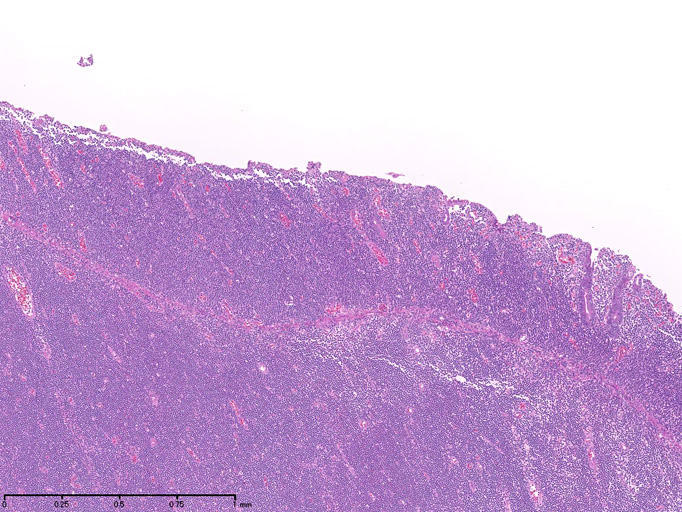

腫瘍細胞は腸管全層に密に浸潤している。粘膜表面は上皮が消失しびらんを形成。(Fig.1), 高倍率では中型, medium sized(組織球の核とほぼ同じサイズ)の類円形核をもつ比較的淡明な細胞質の異型リンパ球様細胞が密にmonotonousな増殖を示している。(Fig.2,3)

粘膜固有層には腫瘍細胞が充満し腺窩基底膜側より陰窩内に進入してIntraepithelial lymphocyte(IEL)の上皮浸潤を模倣する特徴的な蚕食像を示している。(Fig.4)

Pathological Diagnosis: Enteropathy-associated T cell lymphoma, monomorphic type